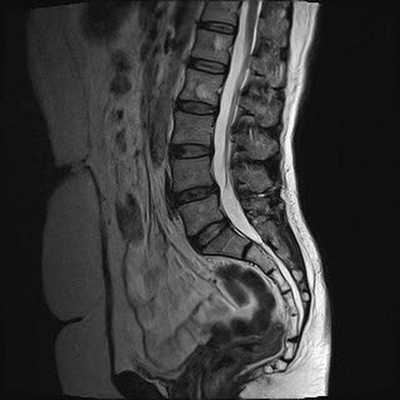

Снимок МРТ поясничного отдела позвоночника в сагиттальной проекции при остеохондрозе

Снимок МРТ пояснично-крестцового отдела позвоночника в сагиттальной проекции (режим STIR)

Снижение высоты диска, секвестрированная грыжа в области тел L4-L5 и абсолютный стеноз спинномозгового канала на МРТ снимке поясничного отдела позвоночника в сагиттальной проекции